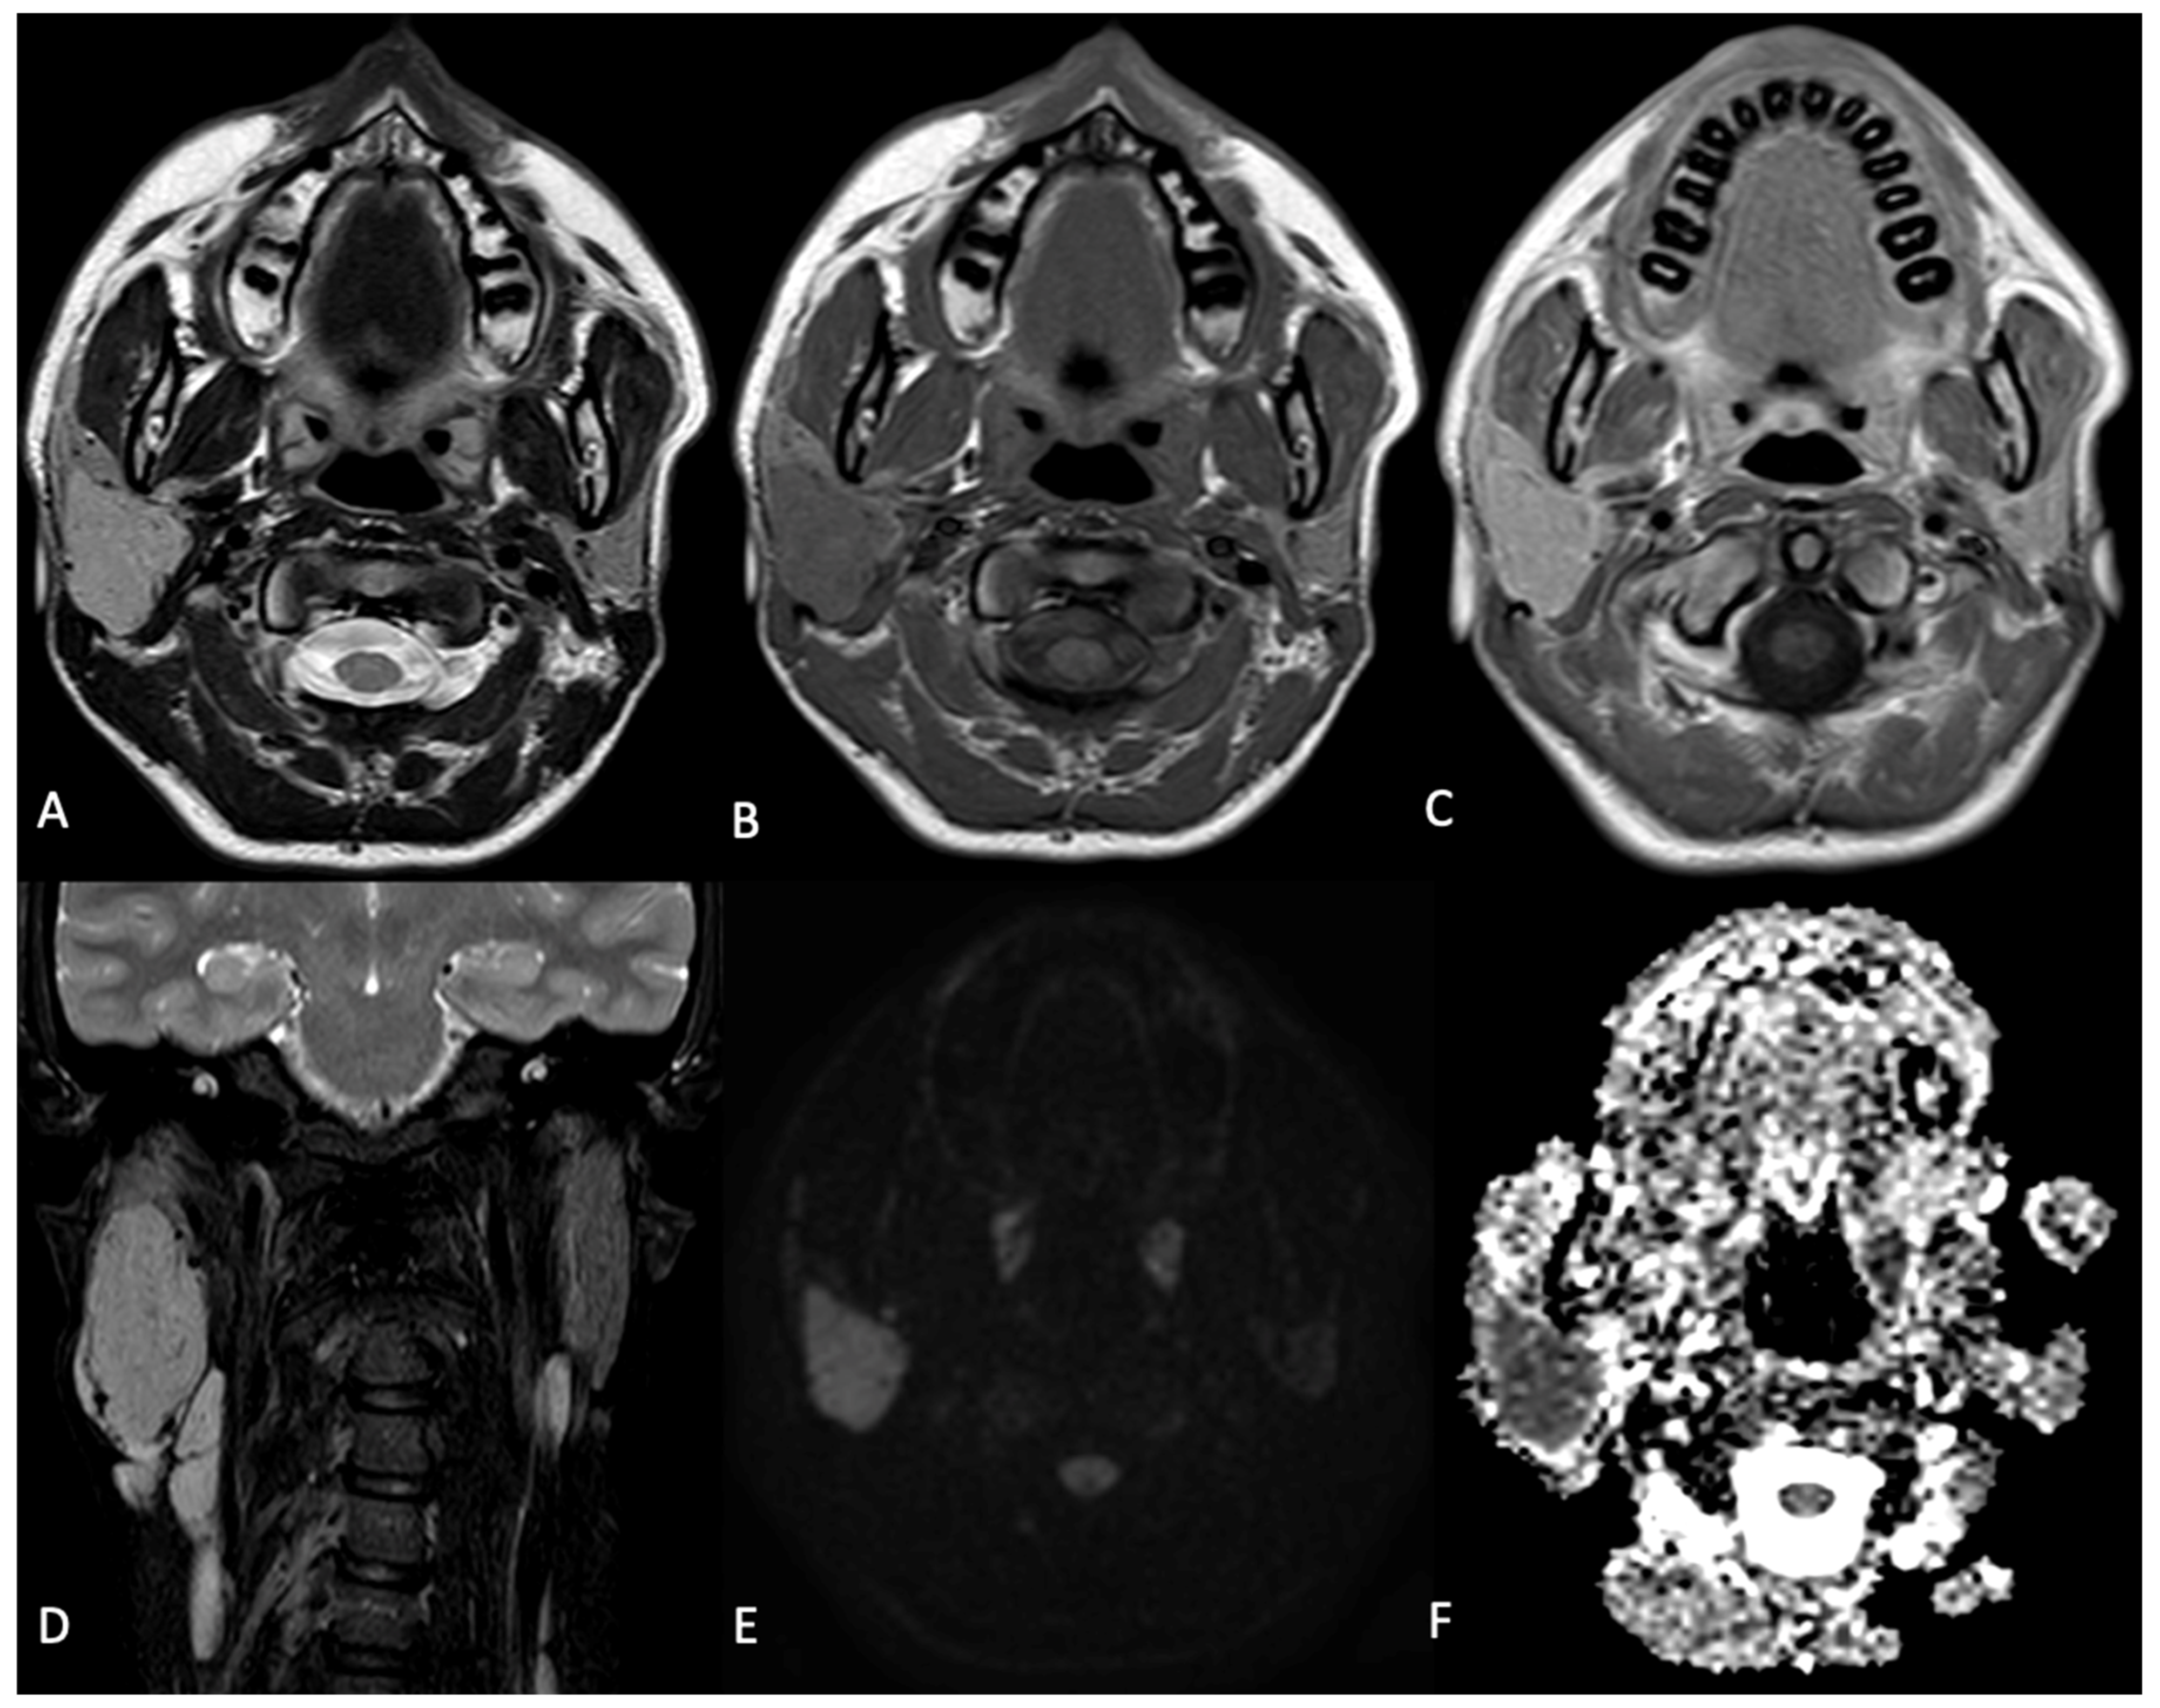

The preoperative embolization was conducted utilizing the direct puncture technique with SQUID 12, employing a biplane flat-panel angiographic system under general anesthesia (Figure 2). A preliminary diagnostic angiographic study was conducted to identify the feeding arteries supplying the mass and to assess for potential extracranial-to-intracranial anastomoses: the digital subtraction angiography (DSA) images revealed a single feeding artery originating from the posterior wall of the right external carotid artery, likely the posterior auricular artery. Additionally, a prominent venous drainage was observed via the facial vein. A 22-gauge needle was inserted into the core of the mass under the guidance of both ultrasound and fluoroscopy. An intra-tumoral angiogram was then conducted through the needle to verify its accurate positioning within the mass. Before injecting the embolic agent, a balloon microcatheter was inflated at the origin of the external carotid artery to prevent retrograde reflux in the internal carotid artery. Subsequently, SQUID 12 was injected through the needle into the mass under fluoroscopic control. At the end of the procedure, the final angiogram showed a total devascularization of the lesion, without any complications.

Figure 2. DSA, anterior-posterior view of the right common carotid artery (A) and lateral (B) and oblique (C) views of the right external carotid artery. The injection showed the blush of the lesion laterally to the external carotid artery (AC), with evidence of a hypertrophic posterior auricular artery (B, black arrow). The lesion was punctured and the needle position was confirmed by angiographic control through injection of the external carotid artery and by an intra-tumoral angiogram obtained after the injection of contrast medium through the needle (D); the main venous drainage of the lesion is clearly visible (D, black arrowhead). The lesion was slowly filled with SQUID 12, until obtaining complete occlusion (E), as confirmed by the absence of blush during the angiographic controls (F).